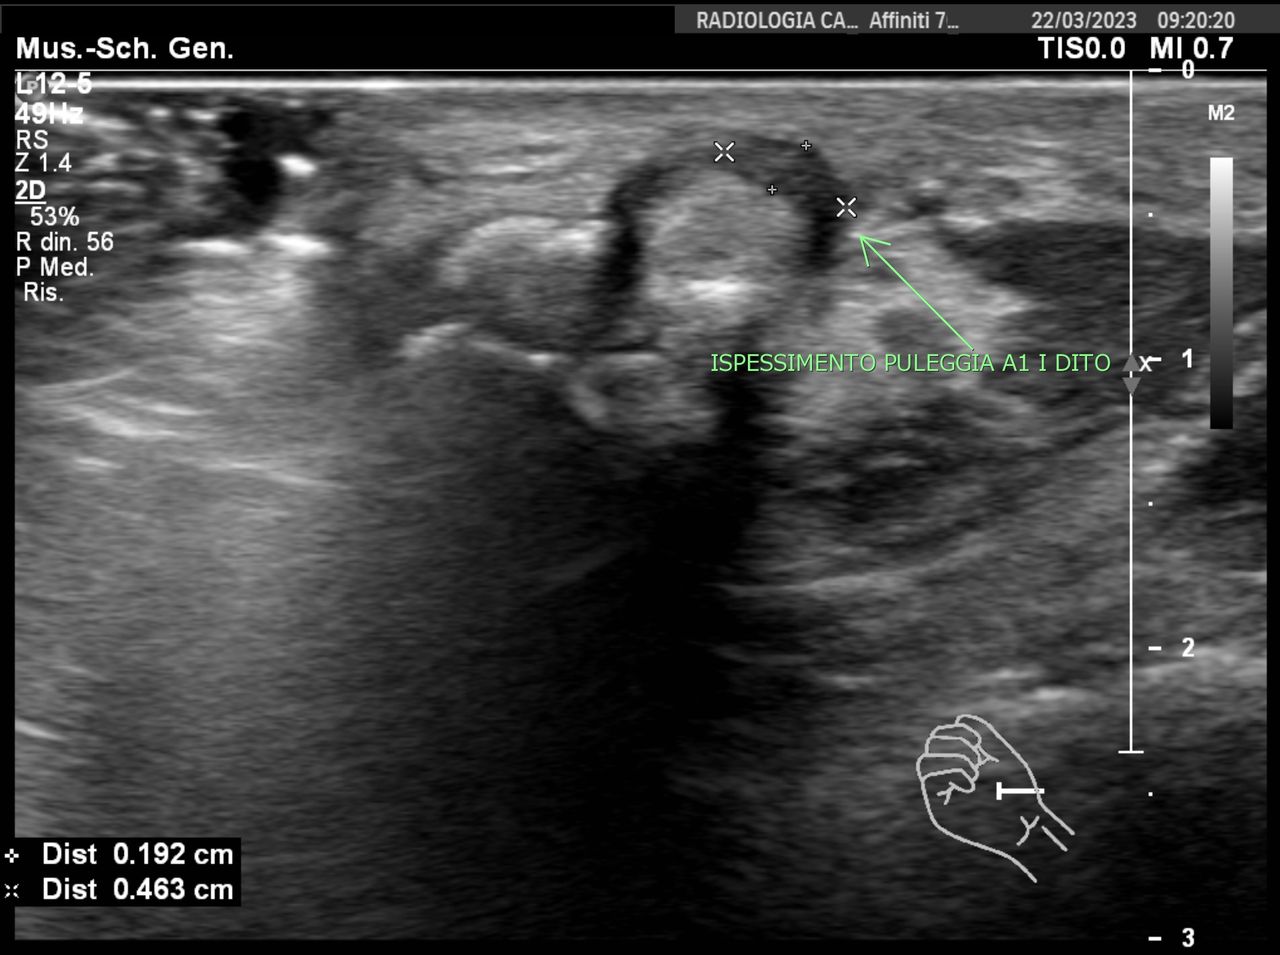

La Dottoressa Morgano Maria Chiara si è laureata in Medicina e Chirurgia presso l’università degli studi di Palermo con 110/110 e Lode. Ha conseguito la specializzazione in Radiologia col massimo dei voti e Lode presso l’università degli studi dell'Insubria. Durante il percorso di specializzazione presso l'Ospedale di Varese "Ospedale di Circolo e Fondazione Macchi", ha acquisito buone competenze diagnostiche come radiologo generale sull'utilizzo di varie metodiche di imaging (RX, ecografia, Tomografia Computerizzata, RM), ma ha dedicato gran parte della sua formazione alla Radiologia Muscolo-scheletrica Diagnostica ed Interventistica, maturando esperienze e competenze nel trattamento ecoguidato di patologie muscolo-tendinee. Ha completato il suo percorso di specializzazione presso "Columbus Clinic Center" a Milano, dove ha avuto la possibilità di seguire un vasto numero di Risonanze su atleti e sportivi come ad esempio giocatori di A.C. Milan, acquisendo competenze specialistiche nell’ambito delle patologie sportive. Ha lavorato come libera professionista presso Vari studi privati nella città di Siena ove praticava l'ossigeno-ozonoterapia sulla colonna per poi lavorare come dirigente medico presso l'Azienda Ospedaliera di Busto Arsizio. Ha lavorato presso l'Ospedale di Carate Brianza, dove ha avviato l'ambulatorio di ecografie muscolo-tendinee ed infiltrazioni eco-guidate. Da gennaio 2026 lavora presso l’ospedale IRCCS Multimedica di Sesto S. Giovanni dove esegue ecografie ed infiltrazioni ecoguidate. Svolge inoltre attività libero-professionale in ambito di Medicina Estetica, integrando alla visita clinica una valutazione ecografica accurata del volto. Questo le permette di utilizzare le competenze ecografiche maturate nella radiologia anche nei trattamenti estetici, al fine di ridurre il rischio di complicanze, indirizzare con precisione l’area da trattare e gestire in modo più efficace eventuali complicanze.

Foto e video